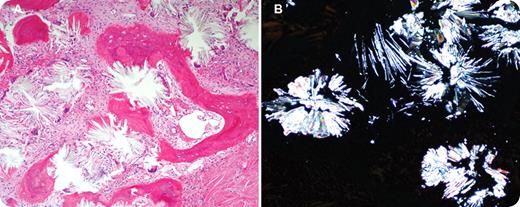

A 28-year-old woman presented with pancytopenia. Her past medical history was significant for primary hyperoxaluria. She had recurrent renal stones and urinary tract infections since the age of 5 years. Subsequently she developed uremic symptoms with end-stage renal disease. For the past 5 years she required regular hemodialysis and transfusions. There was no history of joint pain, cardiac problems, or brain sequelae of oxalosis. On physical examination she had massive hepatosplenomegaly but no lymphadenopathy. Liver enzymes and bilirubin were normal and studies for viral hepatitis were negative. Liver biopsy documented secondary hemochromatosis (transfusion dependent). Laboratory studies showed pancytopenia with hemoglobin of 63g/L, a white blood cell count of 2.6 × 109/L, and a platelet count of 106 × 109/L. Peripheral blood film showed leukoerythroblastic picture with teardrop poikilocytosis. The anemia persisted with little, if any, response to erythropoietin, despite the use of high-dose erythropoietin (100 000 units 4 times per week). Bone marrow biopsy revealed replacement by extensive gray-white crystal deposition (panel A). The crystals were birefringent under polarized light (panel B).

Bone marrow oxalate deposition has been associated with variable degrees of cytopenias, leukoerythroblastic picture, and hepatosplenomegaly. In some patients, as in this case, bone marrow oxalosis can result in resistance to erythropoietin.